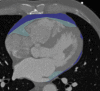

Epicardial adipose tissue (EAT) is a metabolically activated beige adipose tissue, non-homogeneously surrounding the myocardium. Physiologically, EAT regulates toxic fatty acids, protects the coronary arteries against mechanical strain, regulates proinflammatory cytokines, stimulates the production of nitric oxide, reduces oxidative stress, and works as a thermogenic source against hypothermia. Conversely, EAT has pathologic paracrine interactions with the surrounded vessels, and might favour the onset of atrial fibrillation. In addition, initial atherosclerotic lesions can promote inflammation and trigger the EAT production of cytokines increasing vascular inflammation, which, in turn, may help the development of collateral vessels but also of self-stimulating, dysregulated inflammatory process, increasing coronary artery disease severity. Variations in EAT were also linked to metabolic syndrome. Echocardiography first estimated EAT measuring its thickness on the free wall of the right ventricle but does not allow accurate volumetric EAT estimates. Cardiac CT (CCT) and cardiac MR (CMR) allow for three-dimensional EAT estimates, the former showing higher spatial resolution and reproducibility but being limited by radiation exposure and long segmentation times, the latter being radiation-free but limited by lower spatial resolution and reproducibility, higher cost, and difficulties for obese patients. EAT radiodensity at CCT could to be related to underlying metabolic processes. The correlation between EAT and response to certain pharmacological therapies has also been investigated, showing promising results. In the future, semi-automatic or fully automatic techniques, machine/deep-learning methods, if validated, will facilitate research for various EAT measures and may find a place in CCT/CMR reporting.